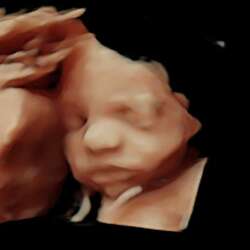

Ik 6+4 ongeveer vandaag, en jij? Wat fijn dat het bij jou snel over is gegaan! Bij mij lijkt er nu niks meer te komen maar er komt weer vast lichtroze vandaag dus ga er niet gelijk vanuit dat het klaar is. Hopelijk nog ff volhouden tot maandag dan heb ik mn volgende echo op 7 weken hopelijk nog steeds een hartje en mooi gegroeide kleintje.🥺

Ik ben 7+3 (dacht 7+6 te zijn maar gister dus drie dagen teruggezet voor nu). Ik heb nu enkel met afvegen nog iets wat beige lijkt en echt minimaal dus ik hoop dat het echt over is nu. Hopen voor jou dat het ook niet aanhoudt, die angst en onzekerheid is vreselijk. Ik duim met je mee voor maandag, dat is dan je 2e echo?🥰